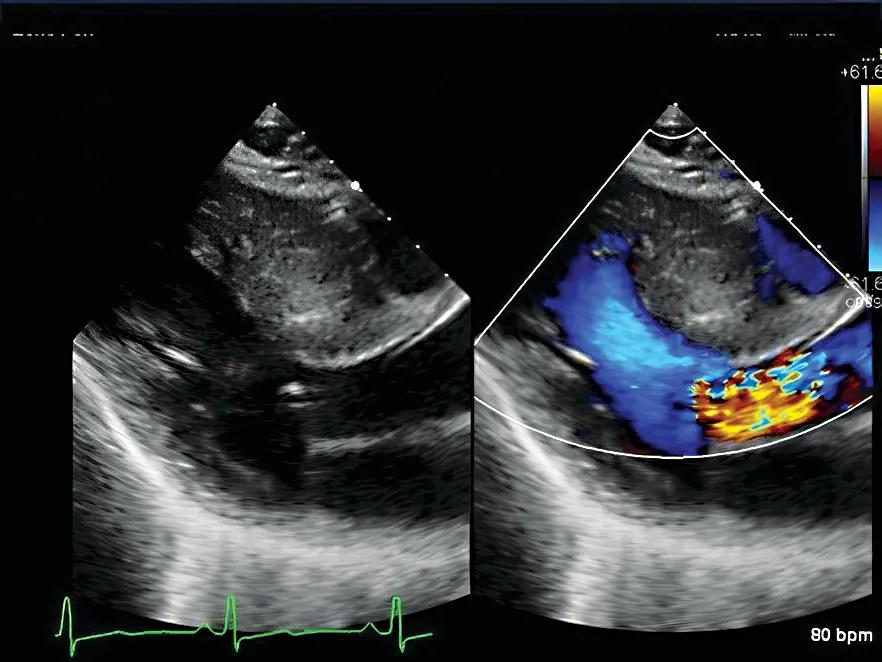

While most patients with HCM have a good quality of life and life expectancy, a wide spectrum of clinical presentations may occur. Because of increased thickness of the heart muscle, heart failure symptoms may develop due to obstruction of blood exiting the heart or from resistance to blood flow entering the heart. In addition, there may be electrical disturbances with HCM that lead to heart rhythm abnormalities including atrial and ventricular arrhythmias and, less commonly, sudden cardiac death.

For all patients with HCM, even for those without symptoms, it is important to have a comprehensive evaluation. This usually requires a complete personal and family history, physical examination, electrocardiogram (EKG), echocardiogram and stress echocardiogram, rhythm monitor and, sometimes, genetic testing and a cardiac MRI. Family screening can be done with interval EKGs and echocardiograms or with gene testing guided by a genetic counselor.